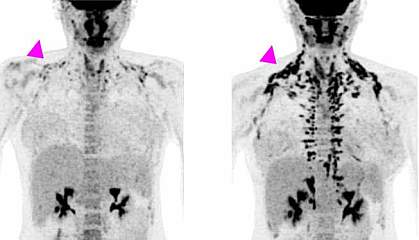

But there’s another kind of fat, called brown fat. Its job is to help maintain body temperature by burning triglycerides to generate heat. Until about 15 years ago, humans were believed to lose most of their brown fat after infancy. It was thought that any brown fat that remained in adults didn’t serve any function. Since then, researchers have learned that nearly every adult human has some functioning brown fat. It’s found only in certain places in people: the neck and shoulders, along the spine, and around the kidneys.

Brown fat may have a big impact on our metabolic health. In mice, activating brown fat reduces levels of triglycerides and cholesterol in the blood. It also prevents atherosclerosis, a sticky buildup along the artery walls that contributes to heart disease. In people, more brown fat is associated with lower rates of type 2 diabetes, cardiovascular disease, high blood pressure, and heart failure. So, having more brown fat, or more active brown fat, may be good for metabolic health. This suggests that increasing brown fat activity might protect against metabolic syndrome.

The simplest way to activate brown fat is long exposure to cold temperatures. But people might not be willing to spend hours a day sitting in the cold. It would be more practical if we could take a drug to activate our brown fat.

Cypess and his team are studying one potential drug, mirabegron, that is currently approved by the Food and Drug Administration for treating overactive bladder. It works by binding to and activating a protein found on the surface of certain cells, including brown fat cells.

In a small trial, Cypess and his team showed that mirabegron could activate brown fat at least as well as cold exposure. In a follow-up study, mirabegron increased the amount and activity of brown fat over the course of the study. The amount of energy used increased, and some measures of metabolism improved, although there were no changes in body weight or the percentage of body fat.